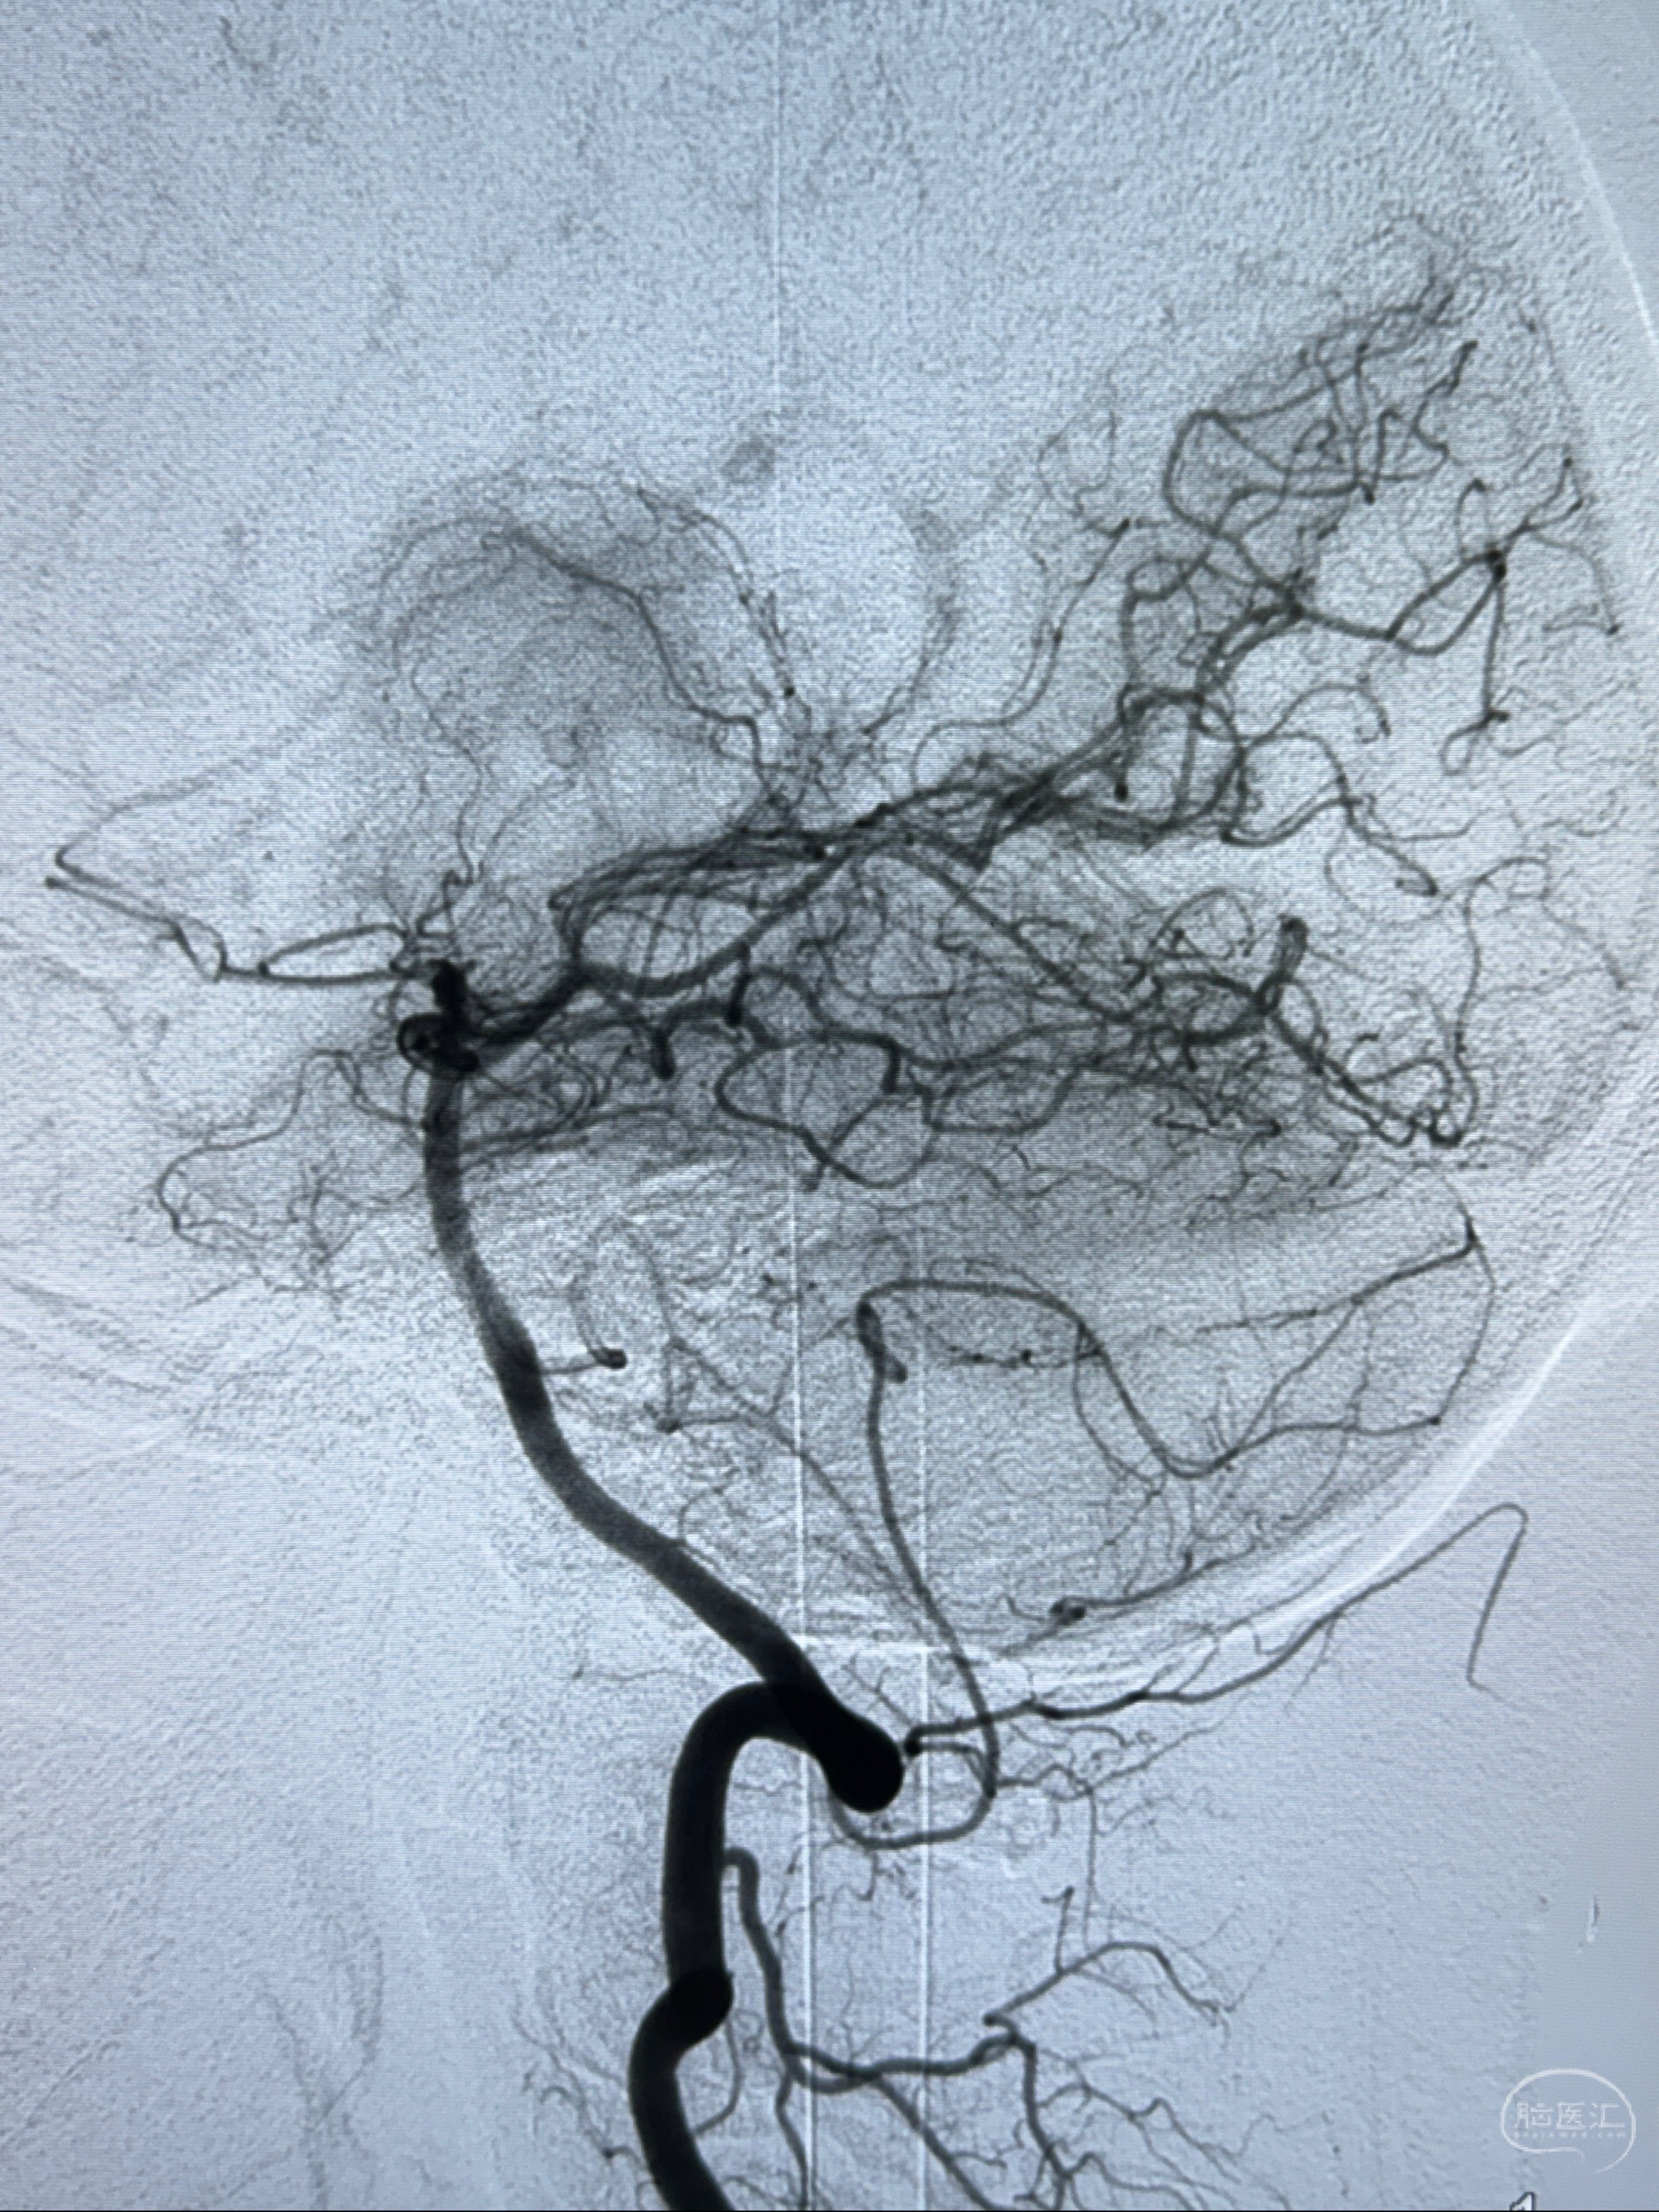

主诉:右侧偏头痛3月,发现左侧颈内动脉眼段动脉瘤5天

现病史:患者诉近4年来时有头痛发作,服用都梁软胶囊、氟桂利嗪对症治疗一月后症状改善,后头痛较少发作。近3月来患者头痛发作频率明显增加,约一月一次,为右侧偏头痛,胀痛,伴恶心呕吐,呕吐后症状可略减轻;遂于2023-11-01至蓝十字脑科医院就诊,查头颅MRI+DWI+MRA提示:左侧枕叶皮层下小斑片缺血或变性灶,右侧大脑前动脉A1段毛糙,显影淡、纤细,建议完善CTA;并于2023-11-03查头颅CTA提示:左侧颈内动脉C6段微小动脉瘤可能(约2mm),右侧大脑前动脉A1段纤细(对侧优势),左侧大脑中动脉提前分叉。现患者无明显不适,为求进一步诊疗颅内血管病变至我科就诊,收治入院。

2023-11-03 蓝十字脑科医院 头颅CTA:左侧颈内动脉C6段微小动脉瘤可能(约2mm),右侧大脑前动脉A1段纤细(对侧优势),左侧大脑中动脉提前分叉。

1.左侧颈内动脉瘤

治疗策略:

- 随访?

- 支架辅助治疗?